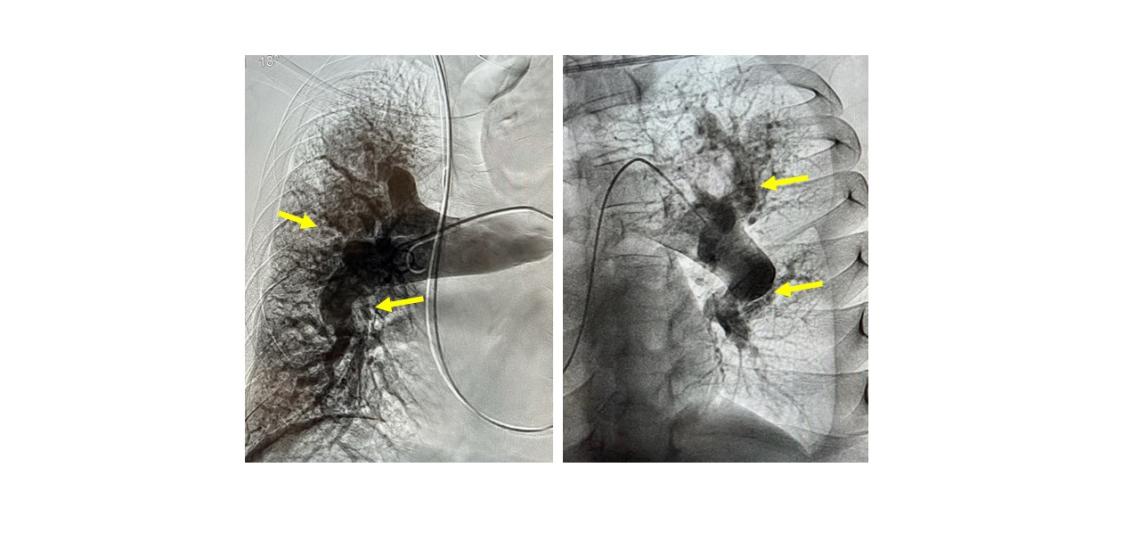

- Pulmonary angiography provides direct visualization of the pulmonary arteries by injecting dye through the blood vessels